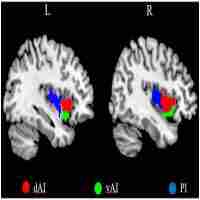

| Abstract | Objective: Clinically, it is very difficult to distinguish between major depressive disorder (MDD) and bipolar disorder (BD) in the period of depression. Increasing evidence shows that the insula is important in depression. We aimed to compare the resting-state functional connectivity (rsFC) of insular subregions in patients with MDD and BD in depressive episodes (BDD), who had never experienced manic or hypomanic episodes when they were scanned to identify biomarkers for the identification of two diseases. Method: We recruited 21 BDD patients, 40 MDD patients and 70 healthy controls (HC). Resting-state functional magnetic resonance imaging (rs-fMRI) was performed. BDD patients had never had manic or hypomanic episodes when they were scanned, and the diagnoses were determined by follow-up. We divided the insula into three parts including the ventral anterior insular cortex (v-AIN), dorsal anterior insular cortex (d-AIN) and posterior insula (PI). The insular-based rsFC was compared among the three groups, and an analysis of the correlation between the rsFC value and clinical scale was carried out. Results: BDD and MDD patients demonstrated decreased rsFC from the v-AIN to the left superior /middle frontal gyrus compared with the HC group. Versus MDD and HC groups, BDD patients exhibited decreased rsFC from the v-AIC to the area in the left orbital frontal gyrus and left superior temporal gyrus (included temporal pole), from the PI to the right lateral postcentral gyrus and from all three insular subregions to the somatosensory and motor cortex. Meanwhile, a correlation between the rsFC value of the PI-right lateral postcentral gyrus and anxiety score was observed in patients. Conclusion: BDD and MDD patients indicate similar decreases in insular connectivity in the dorsal lateral frontal regions, and BDD patients have specific decreased insular connectivity, especially in the somatosensory and motor cortex, which may be used as imaging evidence for clinical identification. |